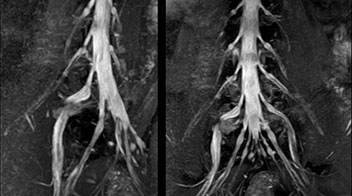

At Northern Fukushima Medical Center in Japan, excellent MRI visualization of nerves helps support confident diagnoses and informs surgical treatment decisions for patients with lower limb symptoms. MRI technologist Tanji and orthopedic surgeon Dr. Yabuki share how direct nerve visualization with the 3D NerveVIEW method adds information when diagnosing atypical herniations. The additional insights changed their way of working and benefit their patient care, as illustrated by some clinical examples.

“In patients with lower extremity neurological symptoms, NerveVIEW helps us to determine the disease matching the patient’s symptoms by directly visualizing the nerves. We use the sequence mainly, when there is suspicion of intraforaminal stenosis, extraforaminal stenosis or lateral disc herniation, which is often based on routine T2- and T1-weighted images. Additionally, the excellent depiction of the course of nerves makes NerveVIEW a good navigator when applying treatment such as block therapy or surgery.”

“In such case, we would then browse through axial T2-weighted MR images slice by slice and mentally reconstruct the actual situation based on both radiculography and MRI. Fortunately, NerveVIEW can now very well show nerve courses and presence of nerve compression or edema in one single image series.” “We have often seen NerveVIEW directly depict details of the nerve compression that were not observed by radiculography. Therefore, we think that with NerveVIEW we can reduce the number of invasive examinations, especially for some patients with lumbar plexus symptoms.”

“The intra-luminal signal of veins, especially around the intervertebral space, can be suppressed well with NerveVIEW. As a result, we can easily observe the detailed nerve structure around the posterior ganglion,” he says. “This is why we use 3D NerveVIEW for intraforaminal stenosis and extraforaminal stenosis/herniation (lateral disc herniation). On the other hand, if herniation is suspected to exist inside the dorsal root ganglion (DRG), balanced TFE or ProSet-FFE is applied. NerveVIEW is not suitable for evaluating the median type of herniation.” The SE-EPI DWI-based method for MR neurography works well for large FOV exams like whole-body MRI, but focal examination of nerves is often limited by the attainable spatial resolution (both inplane and slice direction) and geometric distortion. “3D NerveVIEW achieves higher in-plane resolution – close to our other routine spine sequences – and the source images can be used instead of adding a fat-suppressed T2-weighted sequence,” Tanji says.

According to Tanji, methods such as ProSet FFE, STIR or 3D VISTA are anatomically nonselective because background signals, for instance from blood vessels, often interfere with nerves, which hampers evaluation of details, especially at the peripheral side of the nerves.

“Recently, the two surgical methods extreme and oblique lateral interbody fusion (XLIF and OLIF) have become mainstream for minimally invasive treatment of lumbar spinal canal stenosis and intervertebral foramen stenosis. With these surgical techniques, the spine is approached from the flank, and prior knowledge of the exact anatomy of the lumbosacral plexus would be extremely helpful. To that end, high slice resolution (less than 1 mm acquisition) that enables sharper sagittal MPR images will be needed.”

“For both brachial and lumbar plexus, we are currently using a 230 mm FOV and voxels of about 1 x 1 x 2 mm acquired (1 x 1 x 1 mm reconstructed). This provides us a good representation of the nerves, even though this FOV is relatively small. Regarding the inplane resolution, we hope to be able to bring that down to 0.7 mm, similar to our typical 2D multislice T2W images,” says Tanji.